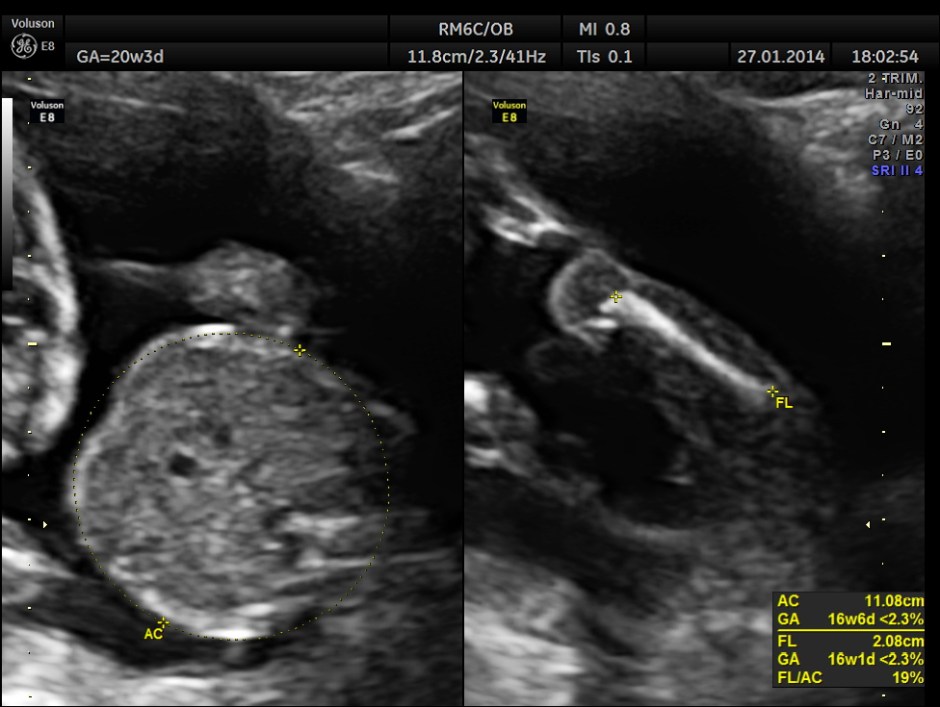

As it can be seen , the GA was around 20 weeks , but the AUA was around 17 weeks. All parameters – BPD, HC, AC, FL are < 2.3 %tile and all other long bones are < 5.0 %tile.